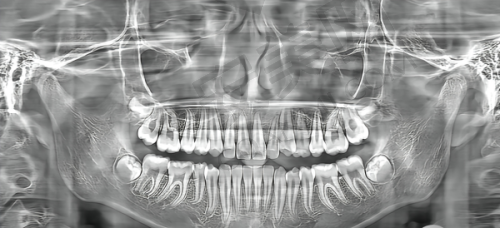

牙齿矫正可以有效改善口腔美观和咬合功能,杭州瑞创口腔医院提供了多种矫正方式供患者选择,不同的矫正方式价格也有所不同。国产金属自锁托槽矫正价格从5000元起,这种矫正方式价格相对较为亲民,适合预算有限的患者;进口金属自锁托槽矫正则需10000元起,进口材料在质量和性能上可能更具优势。国产陶瓷半隐形矫正价格为18000元起,它在美观度上比金属托槽矫正有所提升;进口陶瓷半隐形矫正价格更高,达到22000元起。国产隐形矫正价格从6000元起,进口隐形矫正则要32000元起,隐形矫正具有美观、舒适、可自行摘戴等优点,受到特别多患者的青睐。传统金属矫正价格为6000元左右,而牙齿矫正的整体价格区间在5980 - 38800元起。

镶牙是修复牙齿缺失的常见方法,杭州瑞创口腔医院提供了多种镶牙材料和方式。国产全瓷牙价格从800元起,这种材质美观度高,生物相容性好;国产贵金属烤瓷牙价格为600元起;进口全瓷牙价格在1500元起,进口烤瓷牙价格为1000元起;国产烤瓷牙价格相对较低,500元起。患者可以根据自己的需求和经济状况选择适合自己的镶牙方式。

种植牙是目前修复牙齿缺失比较理想的方式,杭州瑞创口腔医院在种植牙项目上提供了多种选择,以满足不同患者的需求和预算。韩国进口种植牙价格较为实惠,集采价格为1980元起/颗,韩国奥齿泰种植牙价格为4999元起/颗。美国进口种植牙价格相对较高,美国皓圣种植牙价格为8000元起/颗。瑞士进口种植牙属于高端产品,瑞士iti种植牙价格为6980元起/颗,瑞士ITI种植牙价格从6600元起,适合追求更佳治疗成效的患者。此外,杭州瑞创口腔韩国半口即刻种植牙价格为32130元起。总体来说,杭州瑞创口腔医院的种植牙价格在1980 - 6980元起,一颗种植牙不到2025元起步,相对比较平价。

除了牙齿矫正、镶牙和种植牙项目外,杭州瑞创口腔医院的其他口腔项目价格也各有不同。360%舒适化洁牙价格为290元起/次,超声波洁牙价格在28 - 598元左右。补牙根据材料不同,价格从100元 - 870元起/颗不等;全瓷牙冠价格在1499 - 5400元起/颗,具体价格根据品牌不同而有所差异;根管治疗价格为980元起/颗(特定项目);牙齿美白和全瓷贴面的价格因项目而异。美国进口树脂拔牙价格在83 - 659元左右,泽康嵌体补牙价格为3600元左右。儿童全口涂氟价格在7.9 - 400元左右,儿童窝沟封闭价格为39 - 150元左右,微创拔残冠牙/松动牙价格在7.9 - 100元左右,上颌正位智齿拔除等拔牙项目也有相应的收费标准。